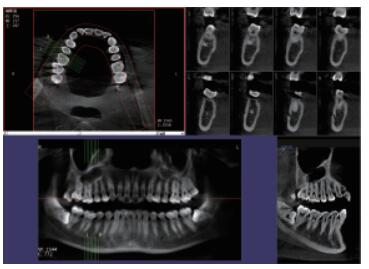

在口腔影像等細(xì)分領(lǐng)域,口腔CBCT的成像質(zhì)量優(yōu)于CT和普放。CBCT的X線利用率更高,且生成的圖像具備很高的各項(xiàng)同性空間分辨率??谇籆BCT能夠針對局部斷層曲面重建生成清晰無重疊的斷層影像以及3D影像,成像效果更好,有助于醫(yī)生的診斷,對于種植、綜合診斷、正畸等牙科診斷均有較大幫助??谇籆BCT技術(shù)優(yōu)勢如下:

三維重建任意斷層

專有三維重建算法,可提供任意位置高清斷層影像。

高清口腔全景影像

通過三維容積影像,提取高清口腔全景影像。

多平面組合重建

可同時(shí)觀察軸向面、冠狀面和矢狀面圖像,方便臨床診斷。